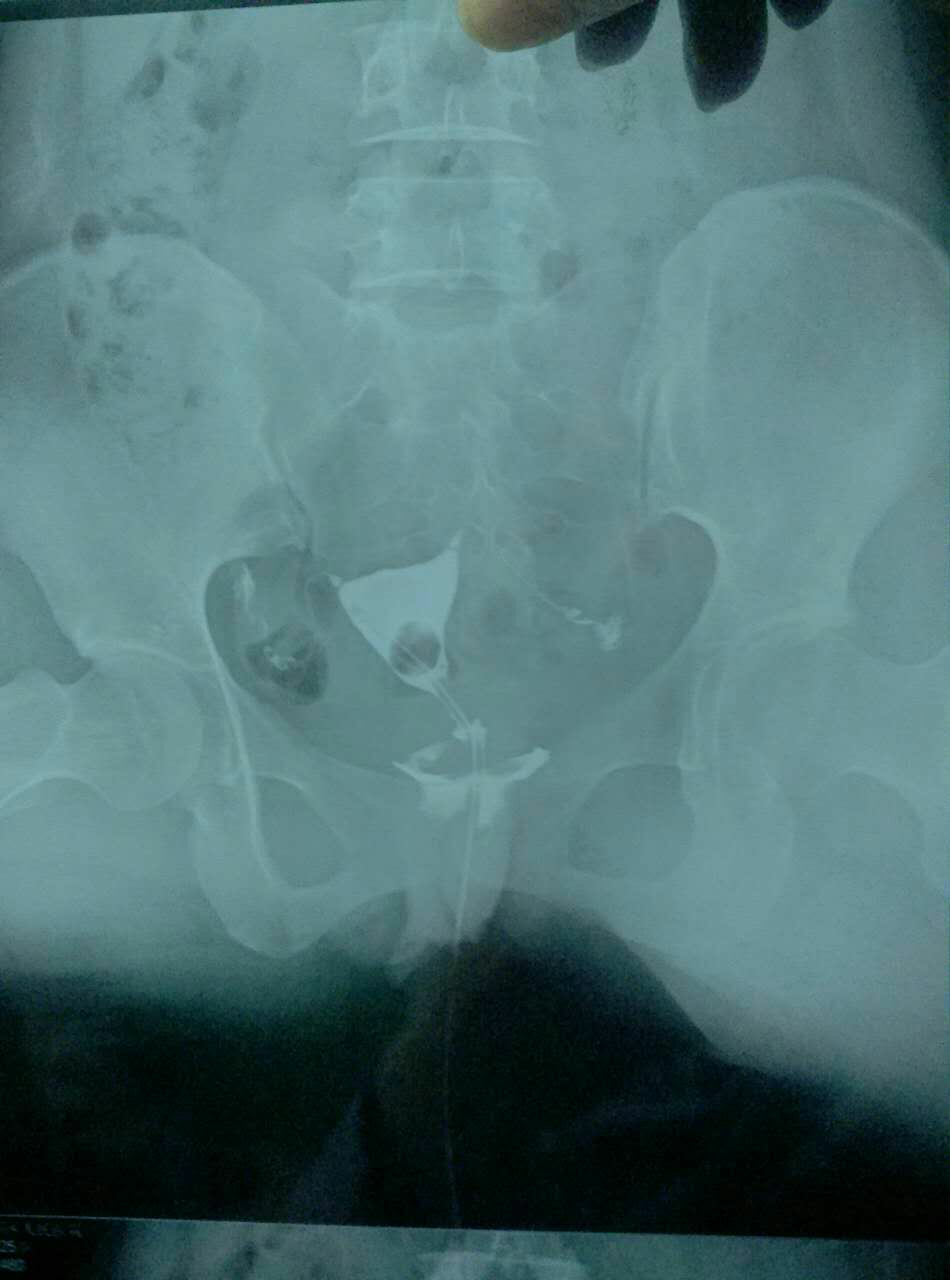

输卵管造影结果,请各位医生帮忙看看 有什么治疗方法?谢谢!

今天做的输卵管造影,请各位医生说说我该怎么治疗。